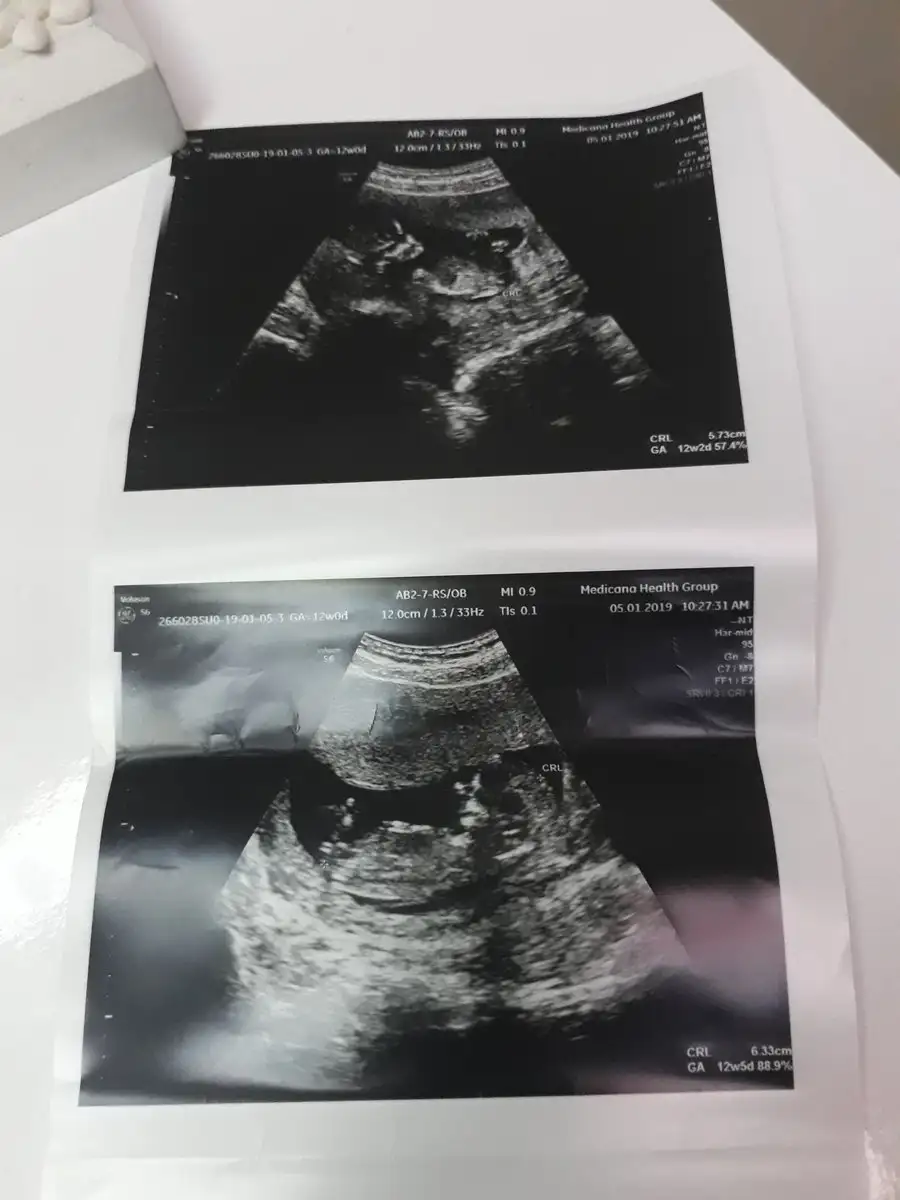

Sagol canimcim. Zatn cinsiyt kismina bakmadm tahmnde bulndu yapidn anliyolr heralde ben kesin dusunmuyorm yine 1 aya kadr:))Canım gözün aydın olsun darısı başımıza resim yükler misin kız gibi demiş ya kesede duruşları fikir verir miş bende çok merak ediyorum meleklerimi

Keseler dibdibe gelms bi cizgi ayiriyo ayaklari geliyor birbirlerinin karsilikli tekmelerler keseyi artik:))Canım gözün aydın olsun darısı başımıza resim yükler misin kız gibi demiş ya kesede duruşları fikir verir miş bende çok merak ediyorum meleklerimi